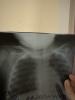

Перелом ключицы у ребёнка

Вчера дочь упала, слезая с дивана. Как итог, перелом ключицы.

Была аналогичная ситуация. В травмпункте сказали после рентгена перелом ключицы. Повязка слетела через пару часов. Мотали сами заново. Потом я смотрю дочка спокойно достает руку и ползает без боли. Уже тогда я поняла что-то не ладное. Поехала за описание снимка и тут шок. Перелома нет! Я бегом без очереди на Фрунзе к ортопеду Альмансуру. Он не мог даже сказать есть перелом или нет. Бред какой-то нанес. В итоге пошла к Шипициной привес замечу без записи ! Что и вам советую не ждать так как с травмой принимают без записи, так вот она посмотрела удивилась всему, что я ей рассказала и сказала нет перелома !

@valery_double, доктор вчера сказал - хорошо, что маленькая, у них все обычно хорошо заживает. Немного стало полегче. У моего папы перелом ключицы со смещением, пластина металлическая стоит уже лет 20. Наверное по этому мы и перепугались так сильно, когда рентген сделали. У меня большая надежда, что в пятницу нас уже нормально зафиксируют. Спасибо, что поделились.